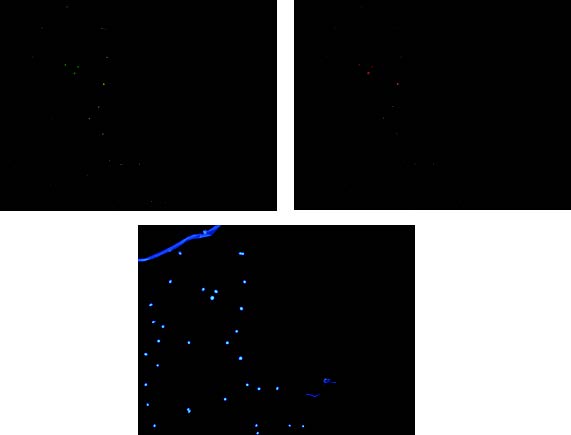

多通道荧光样本